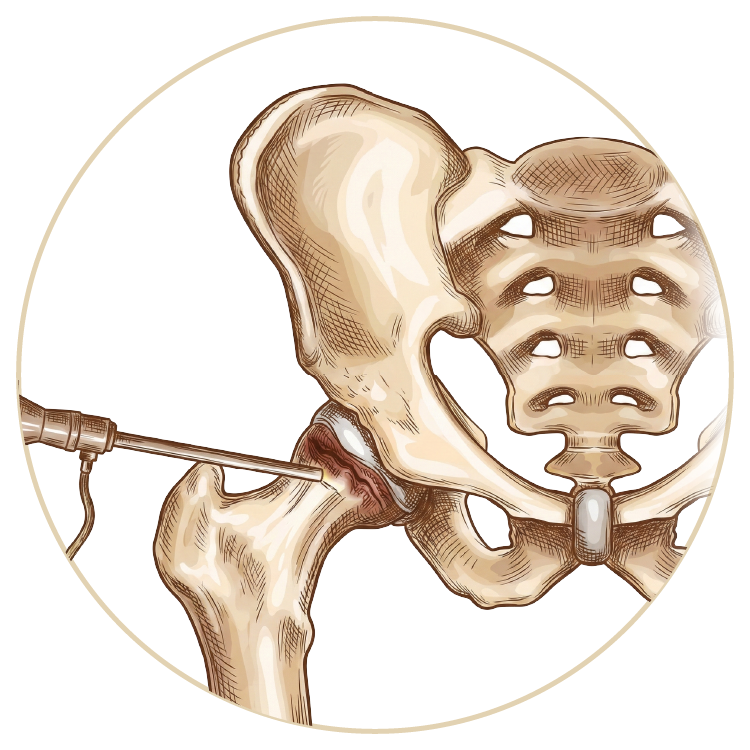

Kalça Hastalıkları ve Tedavileri

Kalça Hastalıkları ve Tedavileri

Kalça Sıkışma Sendromu

Travmatik Kalça Çıkığı

Kalça Artroskopisi

Kalça Protezi

Robotik Kalça Protezi